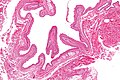

Steatocystoma. H&E stain. | |

| LM | cyst lined by squamous epithelium with a corrugated eosinophilic lining, no granular cell layer |

- Cyst lined by squamous epithelium with:

- Corrugated eosinophilic lining - key feature.

- Similar appearance to compact keratin (hyperkeratosis).

- Described as a hyaline cuticle.[5]

- No granular cell layer.